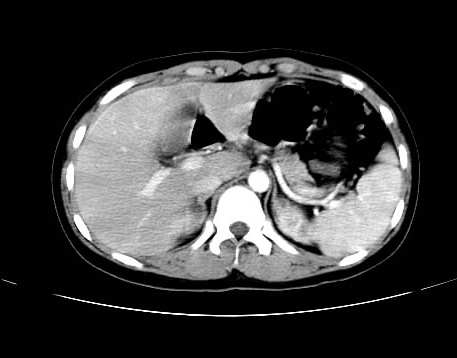

女 16岁  右上腹痛一天,无其他不适

肿块最大径位于十二指肠降段与水平段移行处,并且与肝脏压迹呈“0”形征,可以考虑位于肝外并与胃肠道关系紧密,考虑胃肠道间质瘤(gist)可能较大,须除外神经节起源肿瘤。

肿块与十二指肠关系密切,支持间质瘤诊断.肝脏与结肠均为受压改变.

右下腹巨大肿快,密度不均匀,内见坏死低密度区,边界清楚,与周边胀器明显有分界,未见强化,多考虑来源于间叶组织的良性肿物.

病灶巨大,少部分向肠腔内生长,大部分向长腔外生长。其密度不均匀,增强显示明显不均匀强化,并见有大片状始终不强化的不规则坏死液化区。虽然病灶中上部形态尚可,病人又如此年轻,但中下部形态、密度、强化特点强烈提示为恶性病灶。综上,我考虑本病例为:恶性胃肠道间质瘤。